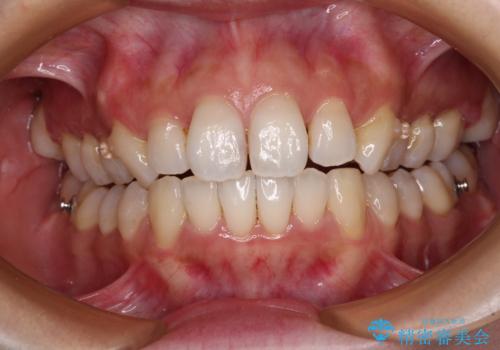

- デコボコと飛び出している前歯を気にして来院された患者様です。

歯列としてはインビザラインでもワイヤー矯正でも対応できるものでしたが、奥歯の咬み合わせを見た時に上顎がやや前方にあり、インビザライン単独では時間のかかってしまう可能性があるため、補助装置を治療当初に使用することで、インビザラインによる治療をスムーズに行えるように計画しました。

インビザラインは得意・不得意の差がはっきりとしているため、補助装置やワイヤー装置などをうまく活用することで、治療期間を短縮するとともに、より理想的な仕上がりを達成することができます。